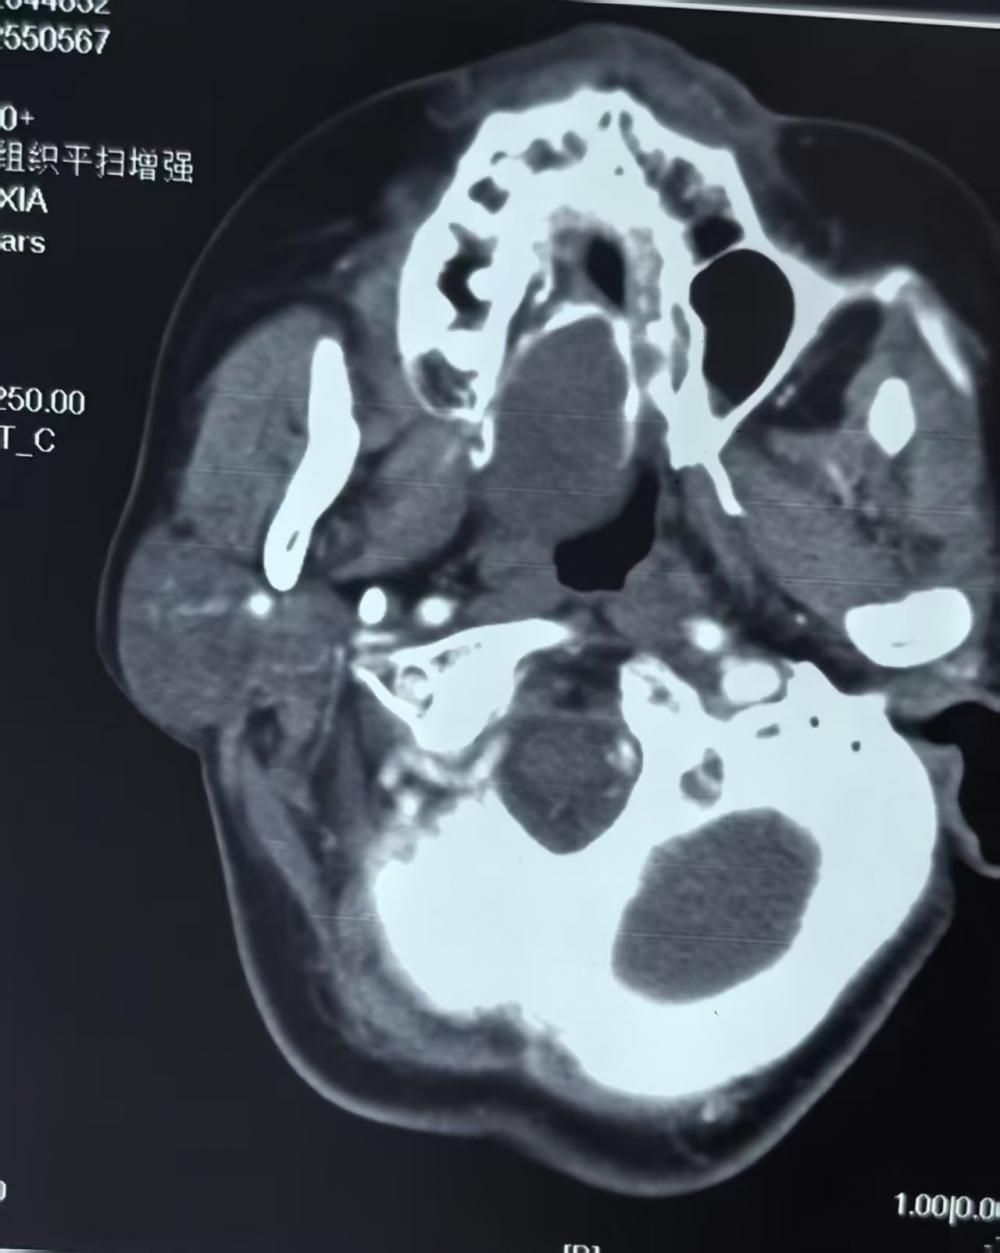

患者王女士(化名)一年前发现右侧腭部隐匿的小肿物,初期未加重视。谁料肿瘤突然生长加速,导致吞咽困难。患者来到徐州市口腔医院,经仔细检查,确诊为"右侧腭部-口咽部交界区巨大肿瘤"。

术前

咽旁间隙被医学界称为"手术雷区",其邻近血管、神经等重要结构,风险较大。面对挑战,医院迅速集结口腔颌面外科、麻醉科精锐力量,经过三次多学科会诊,量身定制了"三维定位+精准剥离"的手术方案,并预设了完善的应急保障体系。

术前检查